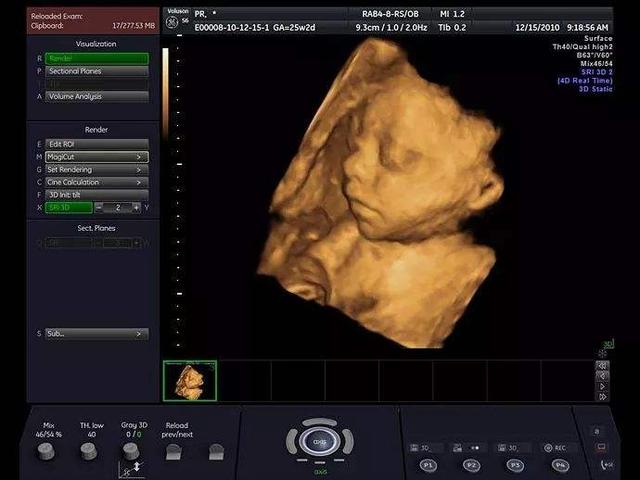

其实,就像朋友这样会对,怀孕四个多月了,那宝宝危害畸形的概率还是很大的,但具体影响有多大,还是要做个四维彩致畸率超才知道怀孕。

四维彩超是在怀孕24周左右做的,可以筛查胎儿颜面畸形、内脏畸形、四肢危害畸形等,怀孕五周抽电子烟有危害吗,孕妇抽烟对胎儿有什么影响大吗而她现在是怀孕四个月,也就是怀孕16-18周了,我让她提前咨询医生,预约四维检查了。